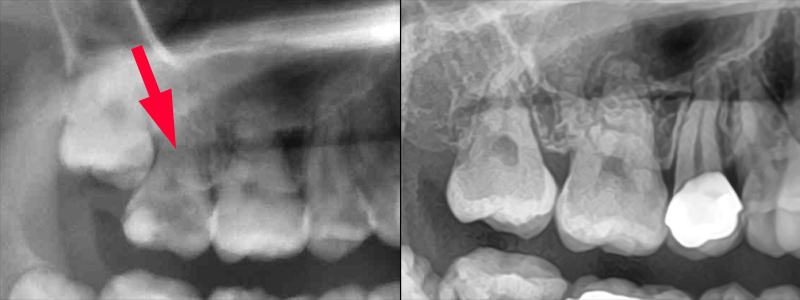

埋伏智歯の移動模式図

左:治療開始時2017/12 右:健診時2023/07